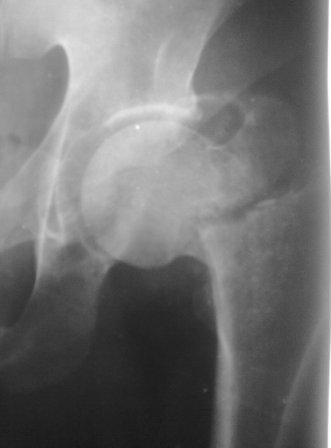

Как предлагали уважаемые коллеги, сегодня наложили спице-стержневой дистрактор таз-бедро, перед этим попробовали закрытую остеоклазию под в/в анестезией, движение в т/б суставе ( или в ложном суставе! ) восстановлен.

Р-снимки сразу п/о, следующий после дистракции, аксиальная - прощу извинения за плохое качество снимков.

Мне кажется надо еще продолжать постепенную дистракцию. И еще которая наверху шейки по моему это осколок от шейки, и она фиксирована оссификатом надвертлужной обл. Поэтому при повторной операции видимо придется открыто мобилизовать т/б сустав.

С уважением Абдурашид.